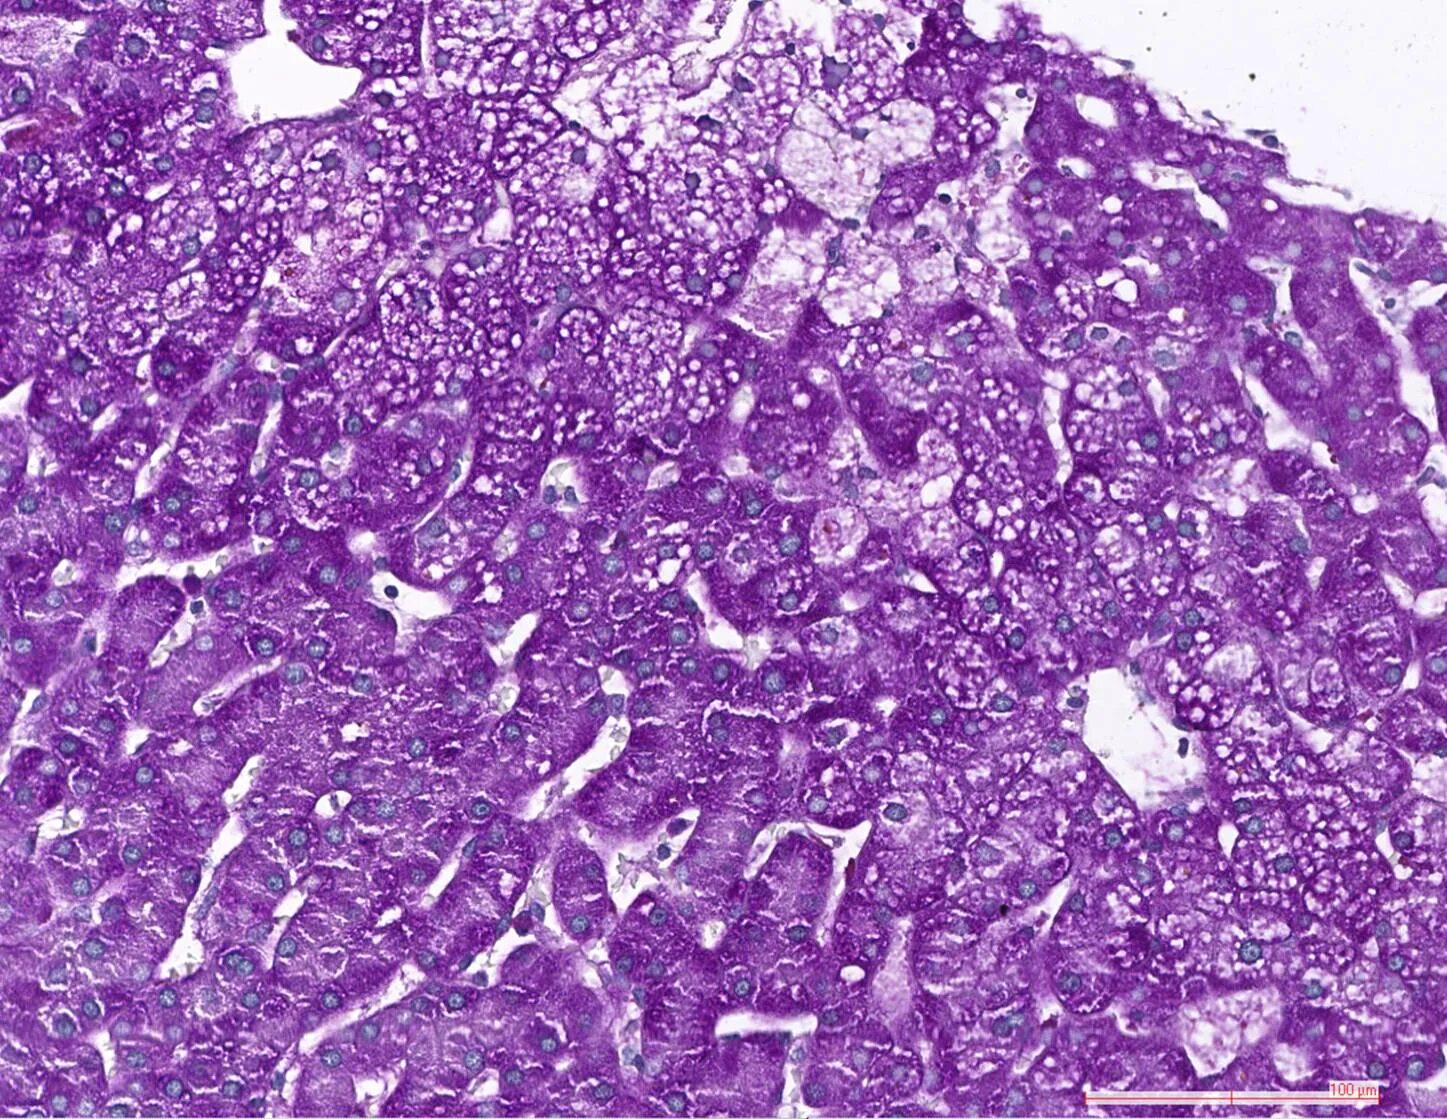

Болезнь ниманна пика тип с тест нмо